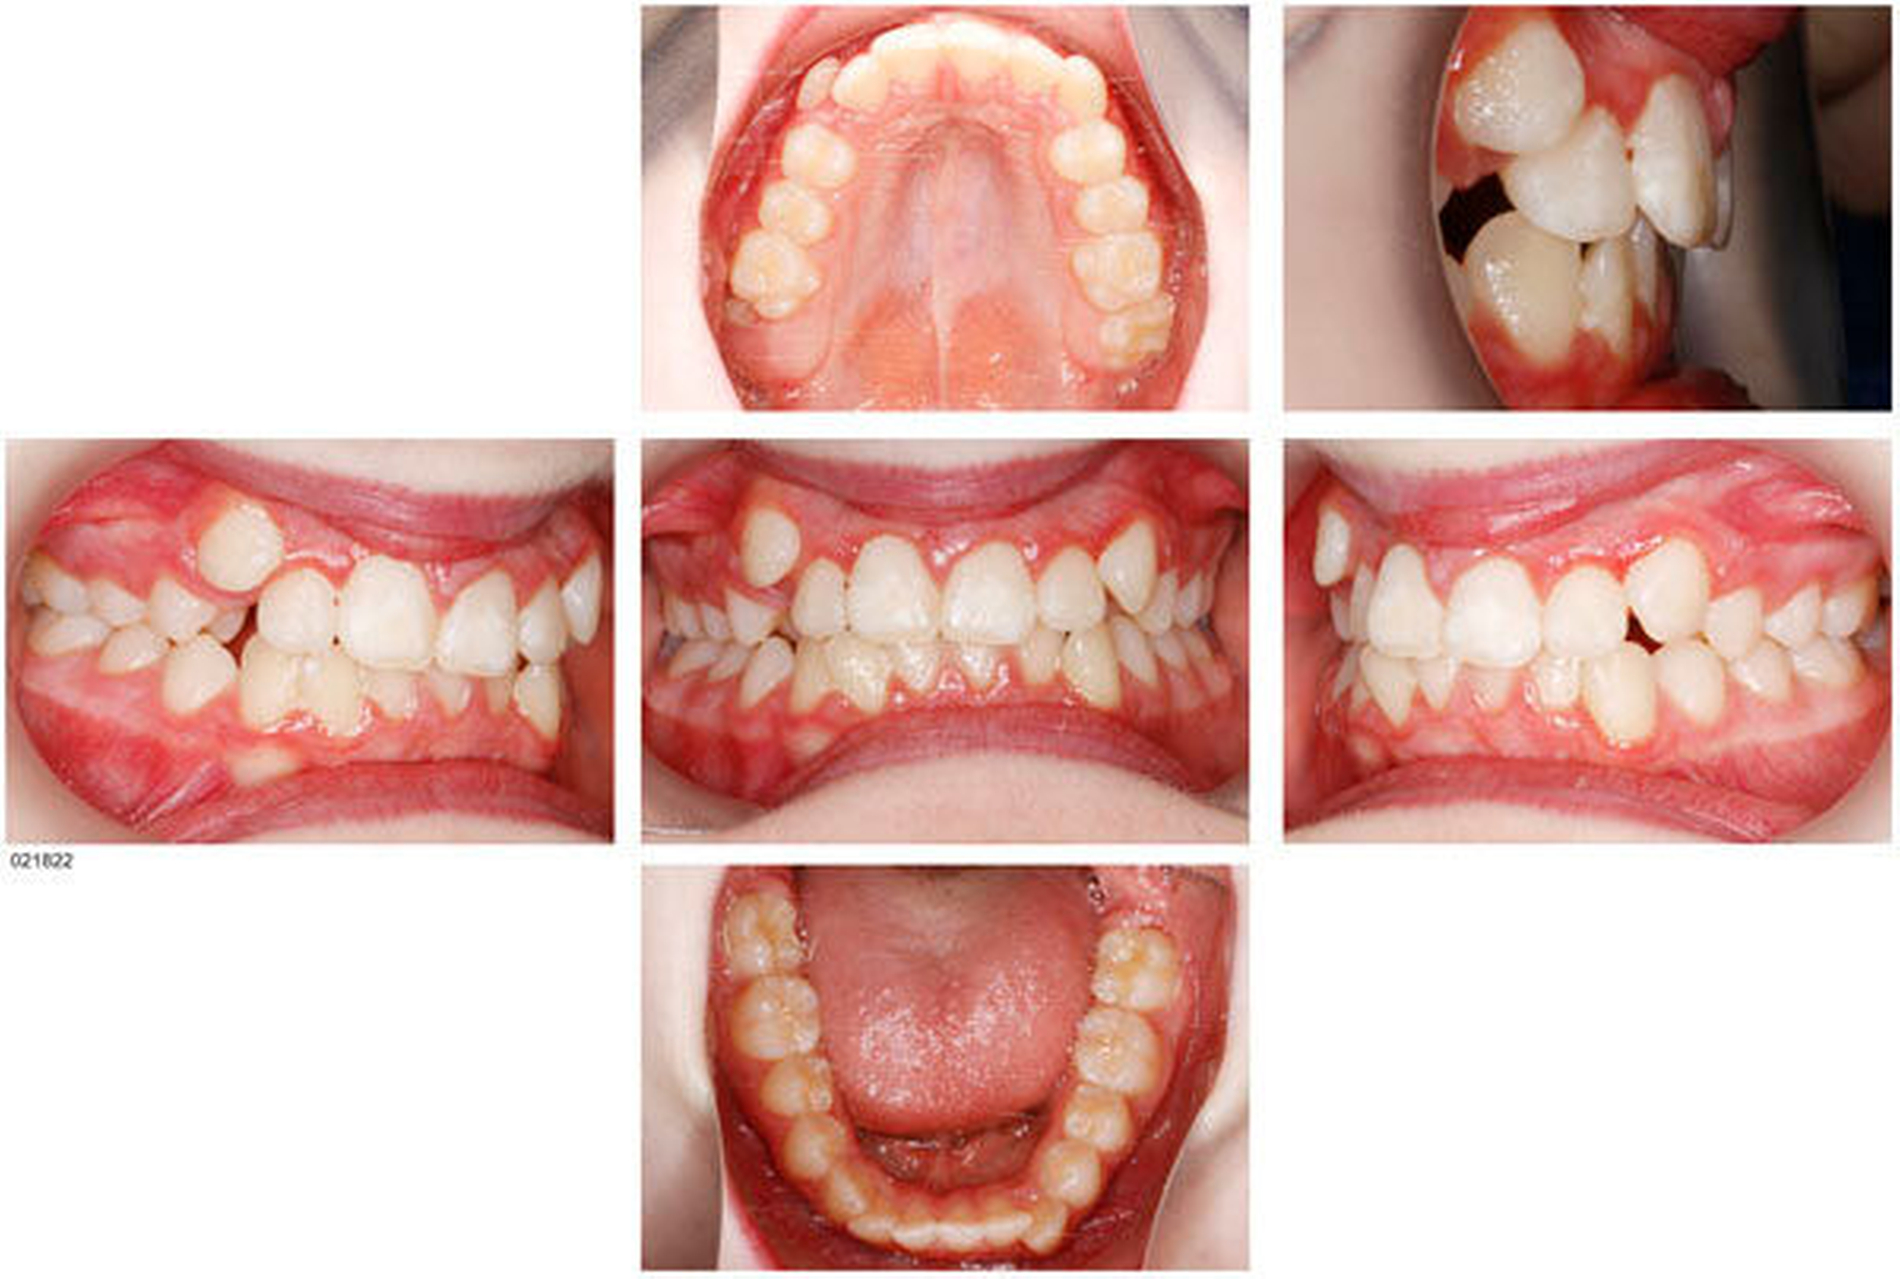

Das Prinzip einer CAD/CAM-gesteuerten Insertion wird anhand einer zehnjährigen Patientin mit einem Platzmangel für die oberen Eckzähne dargestellt (Abbildungen 4a, 4b). Die Behandlung begann mit dem Anpassen von Molarenbändern und einem Silikon-Abdruck des Oberkiefers, der mit dem FRS an das zahntechnische Labor gesendet wurde und dort mit dem FRS der Patientin überlagert wurde. So konnten geeignete Insertionsstellen virtuell geplant werden (Abbildungen 1, 2a, 2b). Nach Rücksprache mit dem Behandler bezüglich der Mini-Implantatpositionen erfolgte die Herstellung der Insertionsschablone (Abbildung 3). Parallel dazu wurde auch der Beneslider [Wilmes, 2010] hergestellt, der zusammen mit der Insertionsschablone geliefert wurde (Abbildung 5). Mithilfe der Insertionsschablone konnten die Mini-Implantate und der Beneslider im selben Termin eingesetzt werden (Abbildungen 6, 7a, 7b). Nach 10 Monaten Distalisierung waren die Molaren in der Zielposition und es war ausreichend Platz für die Eckzähne vorhanden (Abbildungen 8a, 8b), so dass Brackets für die zweite Phase der Behandlung eingesetzt werden konnten. Die Multibracket-Apparatur (Abbildung 9) konnte nach 12 Monaten entfernt werden (Abbildungen 10, 11).